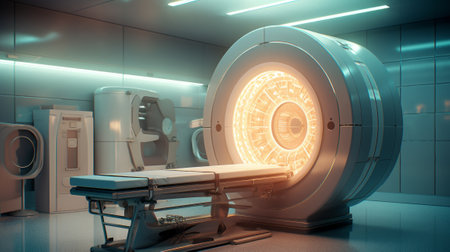

mri scan machine Generative AI

3d rendering x-ray machine in hospital room with glowing lights

The MRI room of the future

A state-of-the-art MRI machine in a high-tech medical imaging room with multiple screens displaying brain scans.

CT ( tomography) scanner room in hospital. Generative AI